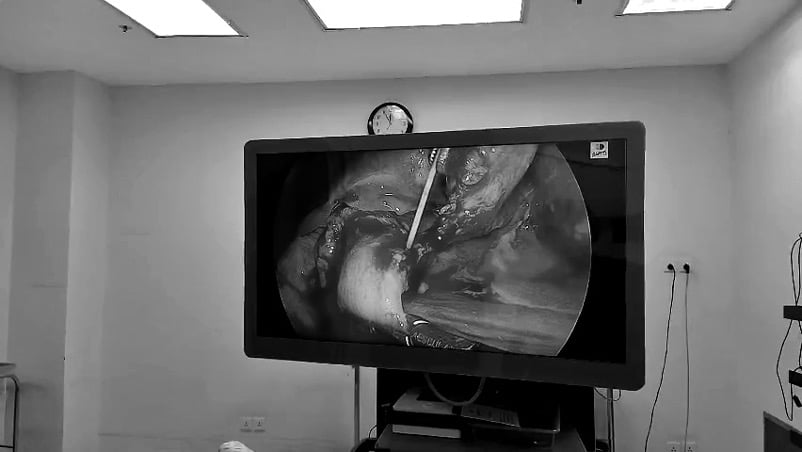

Quá trình phẫu thuật nội soi ghi nhận: Ổ bụng có dị vật xương cá đâm thủng dạ dày, ekip bác sĩ đưa ra hướng xử trí là lấy xương cá, khâu lỗ thủng dạ dày. Sau phẫu thuật, hiện tại, tình trạng cụ bà dần hồi phục, giảm đau bụng nhiều so với trước mổ, có thể ăn nhẹ và đang được điều trị tại Đơn vị Tiêu Hóa, dự kiến xuất viện trong vài ngày tới.